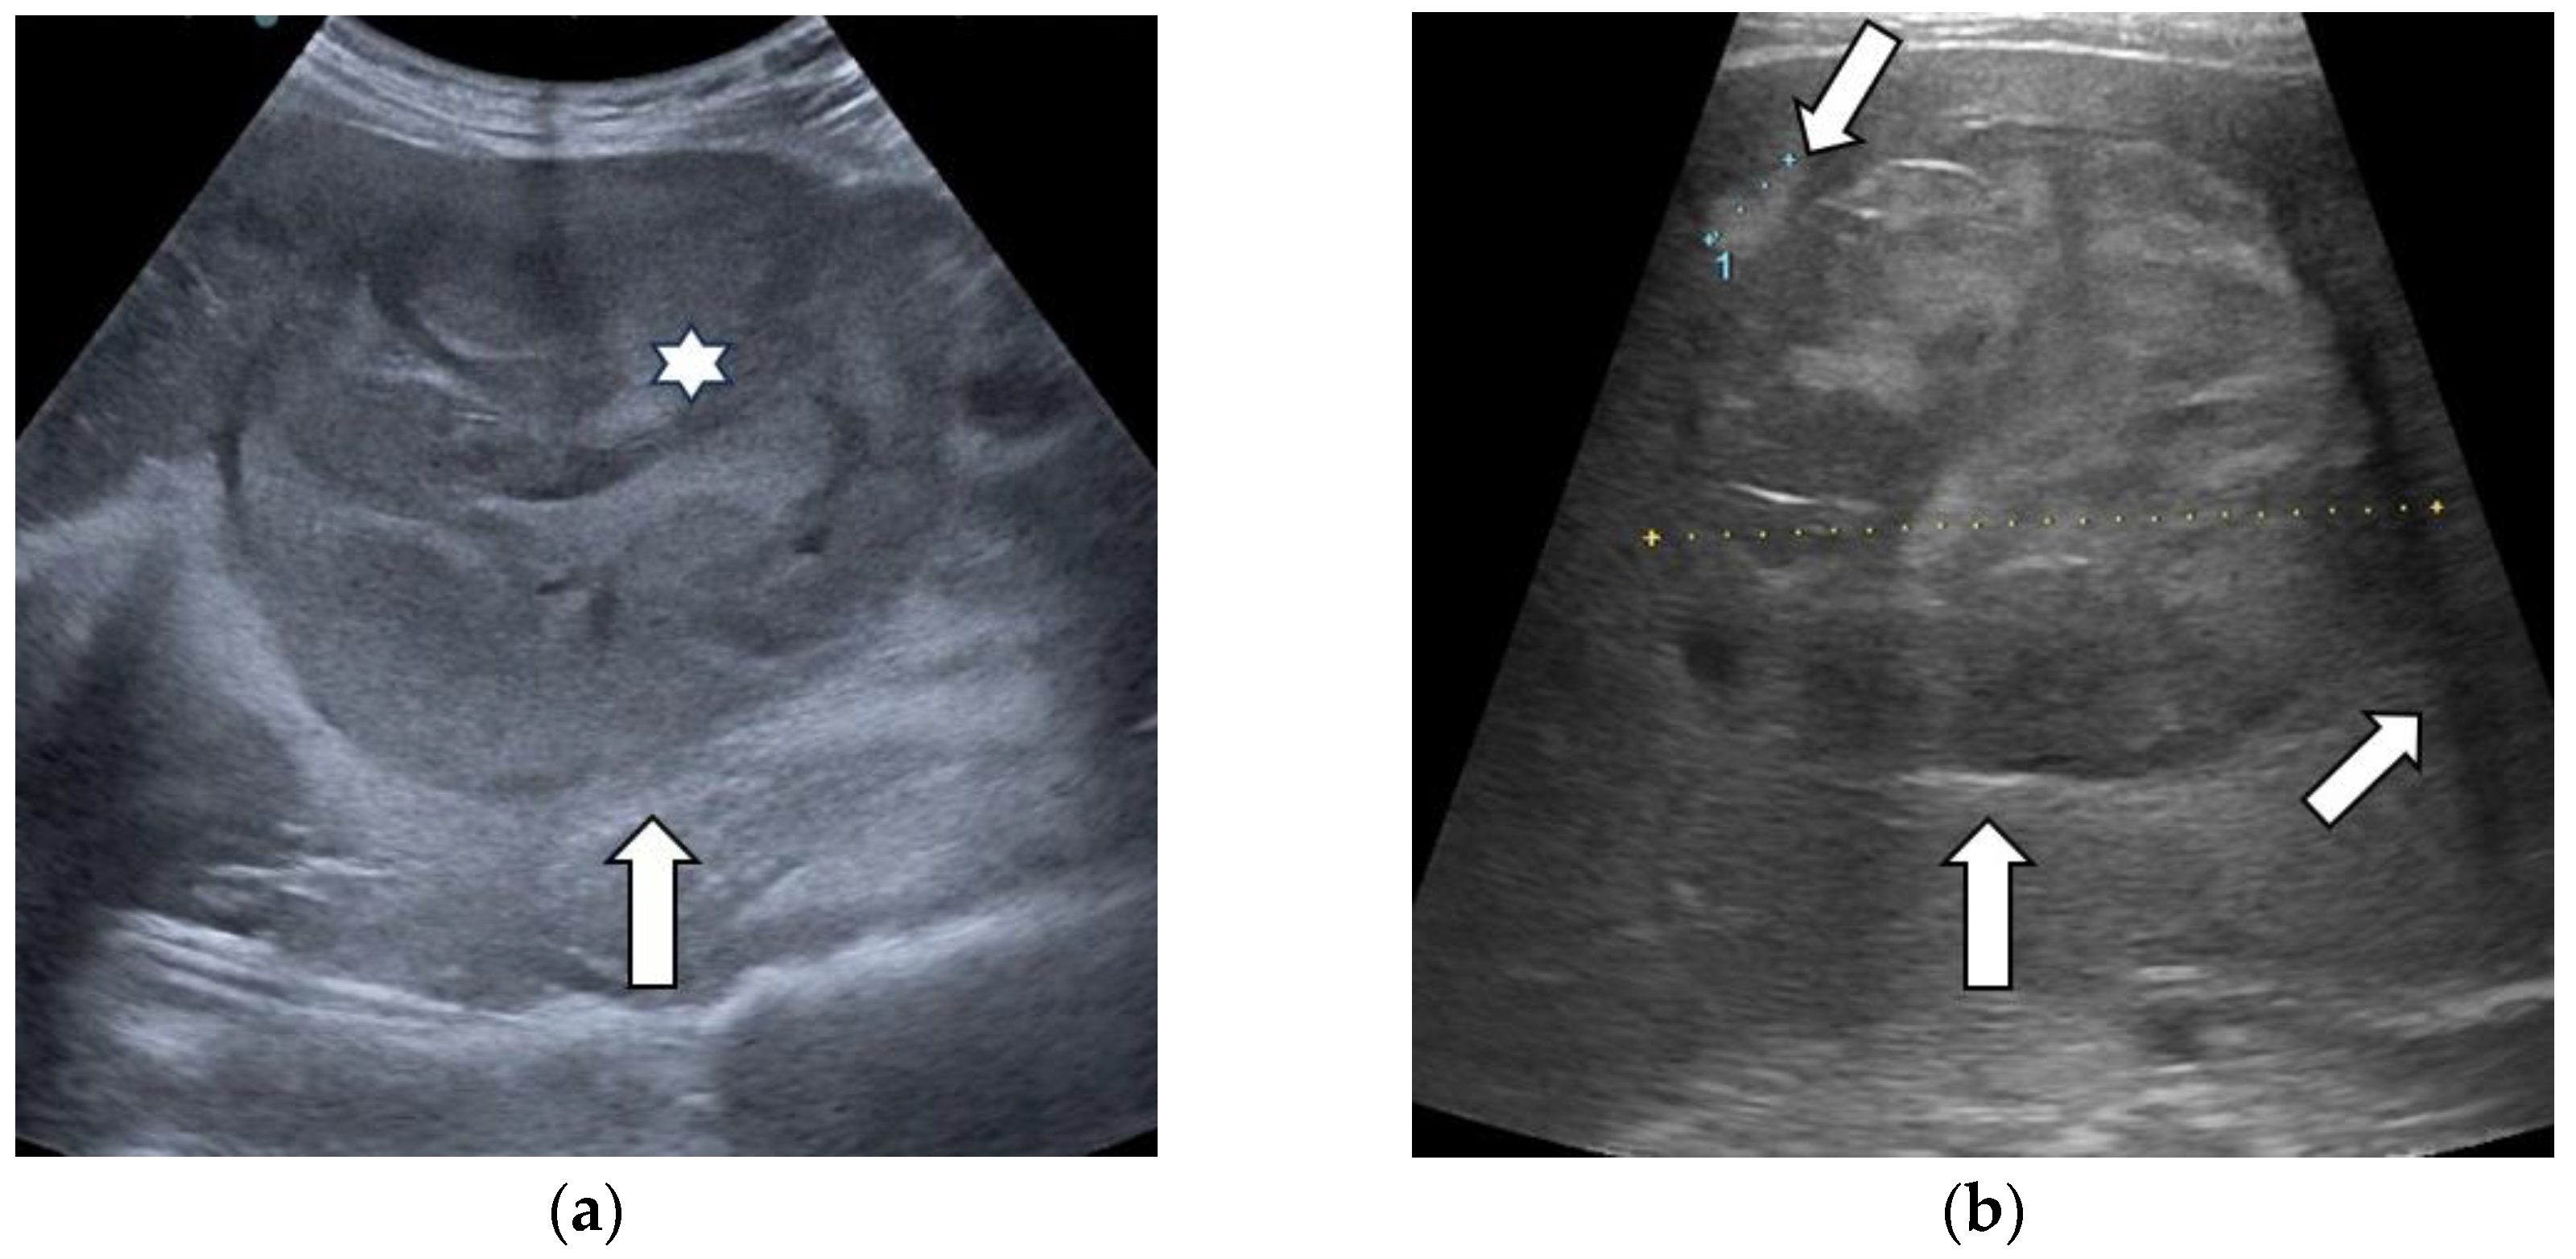

3.1. B-Mode Ultrasound

| "Nodule-in-nodule” architecture | Yes | 18 (25%) | 17 (23.61%) | 1 (1.39%) | 0 |

| No | 54 (75%) | 27 (37.50%) | 16 (22.22%) | 11 (15.28%) | |

| Mosaic appearance | Yes | 16 (22.2%) | 16 (22.2%) | 0 | 0 |

| No | 56 (77.8%) | 28 (38.89%) | 17 (23.61%) | 11 (15.28%) | |

| Halo sign | Yes | 28 (38.9%) | 21 (29.17%) | 5 (6.94%) | 2 (2.78%) |

| No | 44 (61.1%) | 23 (31.94%) | 12 (16.67%) | 9 (12.50%) | |